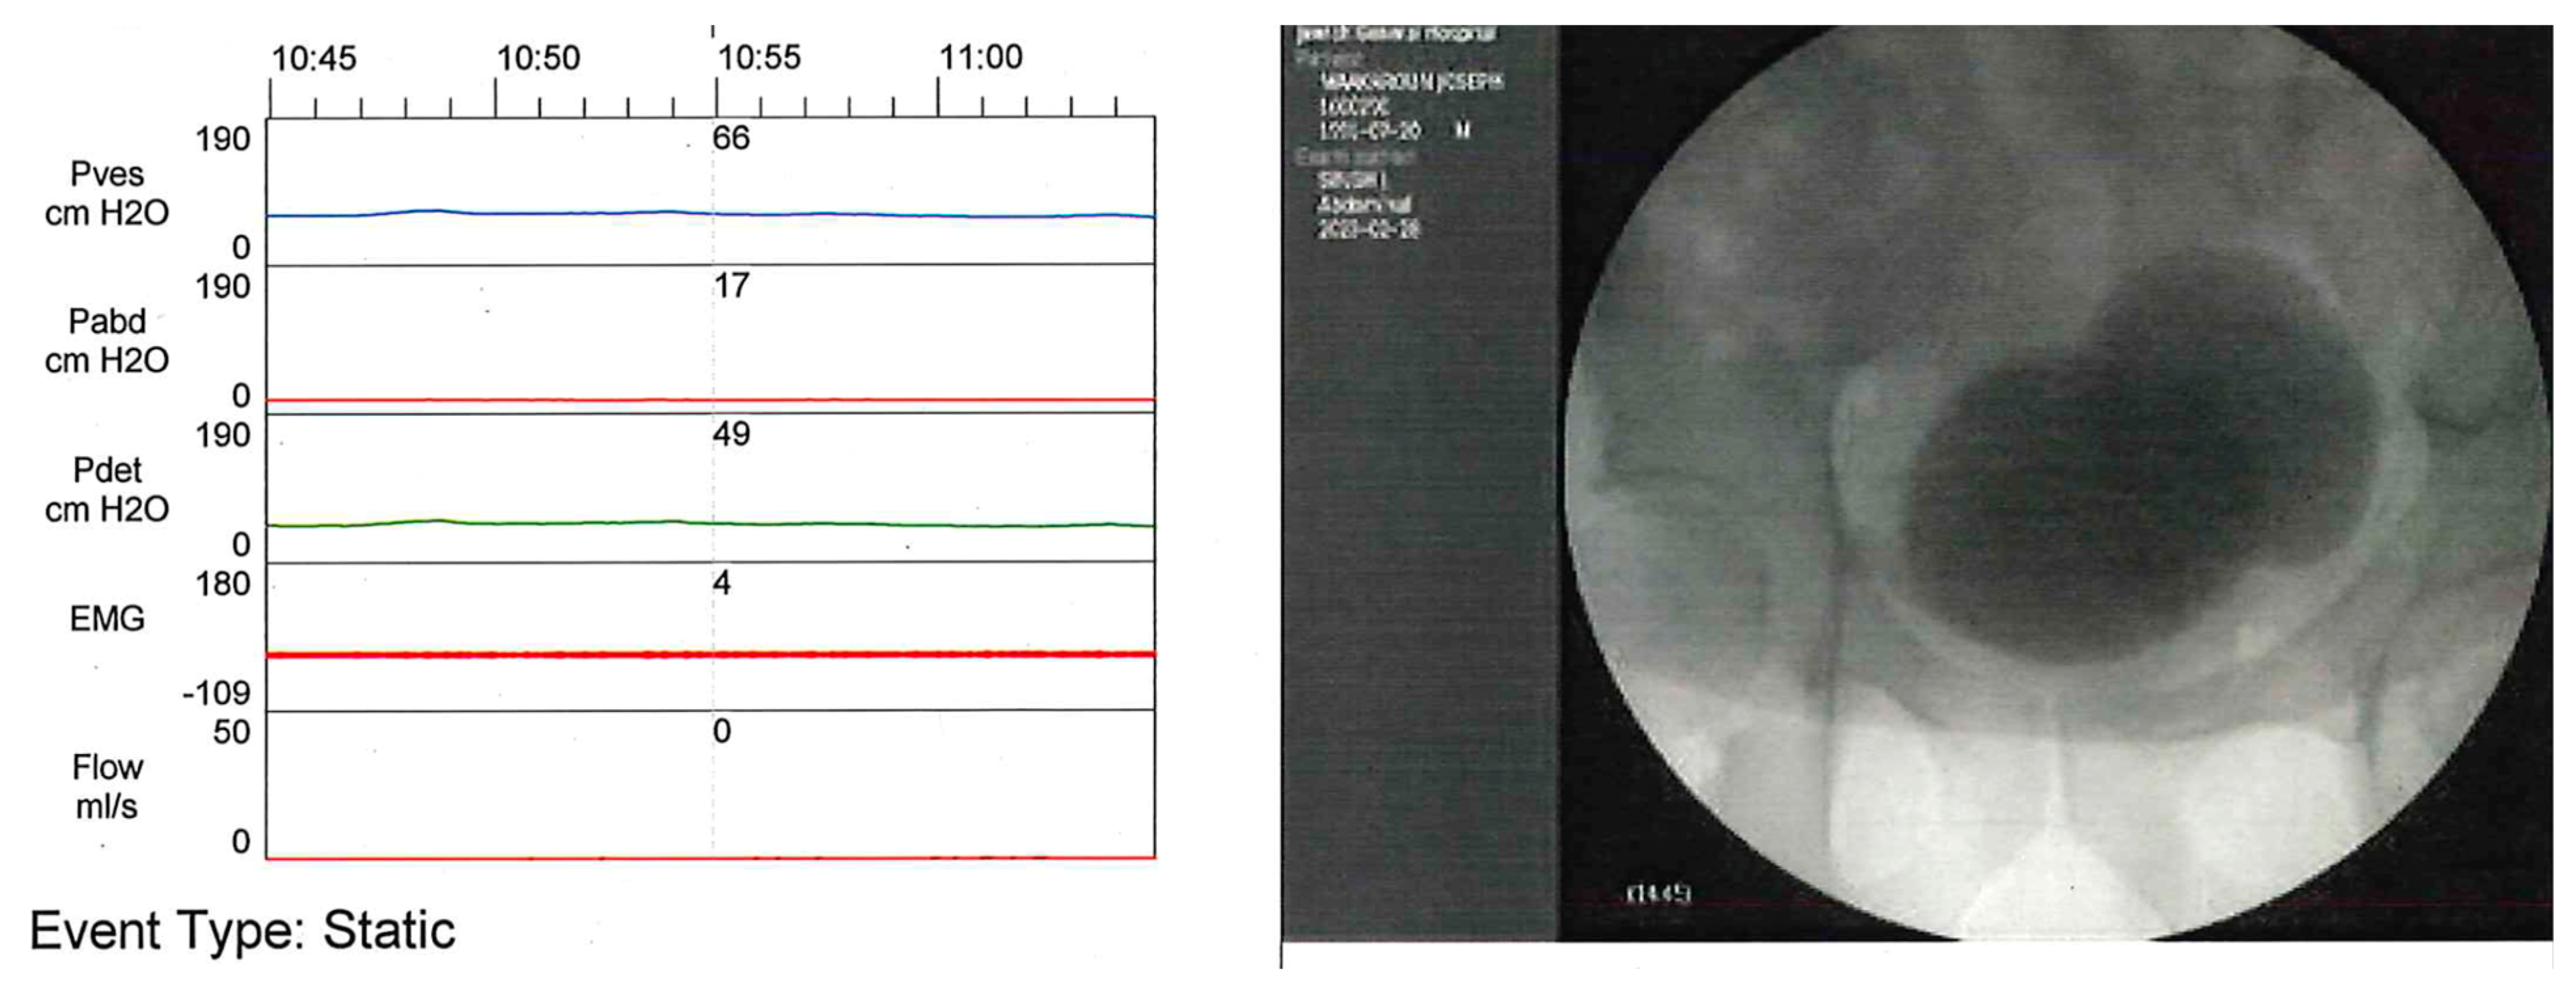

- Type 1 DSD presents a progressive increase in the external urinary sphincter (EUS) activity, with a peak at maximal detrusor contraction followed by a quick relaxation of the EUS as the detrusor pressure declines, allowing urination.

- Type 2 DSD shows clonic contractions of the EUS intermittently during the detrusor contraction, provoking intermittency of the urinary stream.

- Type 3 DSD is characterized by a continuous EUS contraction during the entire detrusor contraction, resulting in urinary obstruction or inability to urinate.